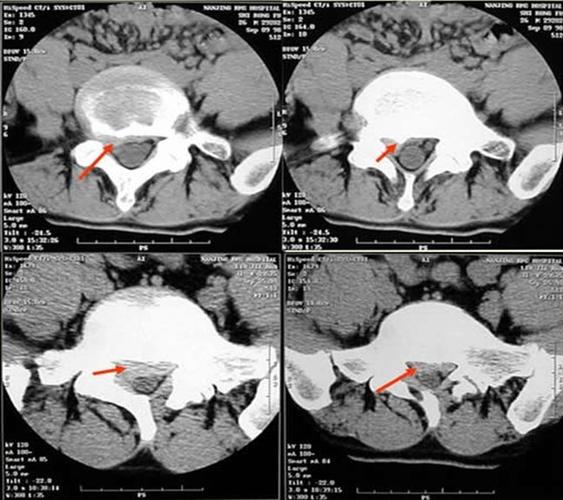

椎间盘突出示意图 轻度膨出时表现为椎间盘后缘正常肾形凹陷

ct检查显示单纯"腰椎间盘突出",这并不是病!盲目治疗不可取

腰椎间盘突出ct图片

腰间盘突出照片ct真实